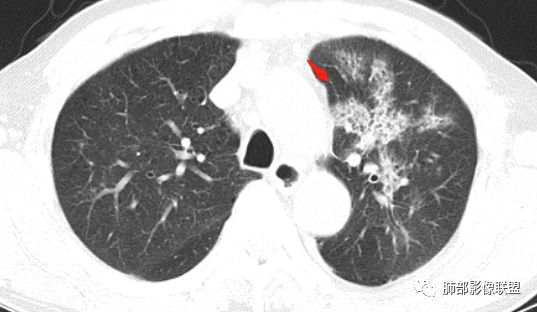

背段支气管有问题,局部有结节

膈面上还有一个结节

总共4处病灶,如何考虑?

左肺上叶病灶长轴与支气管走形一致,提示沿支气管分布病变,倾向于炎性,大家可能怀疑这个病例是来源于胸膜下为主的,胸膜下来源首先整体是来源于胸膜下,与胸膜下之间没有间隙,而这例与胸膜下有间隙。而且这个病变是沿支气管朝外蔓延的,而胸膜下来源的是朝内蔓延的,唯一给我们错觉的是靠近纵隔胸膜这个地方有问题。但是靠近纵隔胸膜这个位置实变不是靠近胸膜实变,它边缘收缩的,没有膨隆的迹象。我们看到里面支气管直达远端稍扩张,是以中央间质为主、小叶间隔朝外蔓延,有间质也有实质病变,走向是沿中央间质方向走的,我个人倾向炎性病变。    问题是右下叶病灶怎么解释?右隔上、右肺门各有一个结节。这个病人有急性咳嗽、胸痛的病史,还有糖尿病病史,周围渗出比较明显,应该警惕炎性病变,要警惕克雷伯杆菌、结核、金葡菌霉菌,因为糖尿病人经常好发这些病菌感染。那么右下叶病变怎么考虑?能不能一元论?    左肺病灶是一个急性渗出为主的病变,一个急性感染的迹象;右肺下叶背段结节,没有看到支气管,增强图支气管壁增厚,局部小结节,呈分叶状,支气管堵塞,没有粘液栓样指套样改变,但是里面有强化,我倾向于癌,其次待排结核。我还是倾向于癌的可能性,恶性可能性大一些,可惜我看不到支气管腔内。还考虑有没有淀粉样变性的问题,弥漫钙化灶最常见的一个是结核,另一个是淀粉样变性。叶段支气管壁有弥漫增厚的迹象。所以淀粉样变性跟结核都要考虑。

鳞癌起源于支气管粘膜,是气道中最常见的恶性肿瘤,易造成支管壁增厚,并突入腔内形成结节,造成狭窄、阻塞或截断;早期鳞癌表现为沿支气管生长的梭形结节或局限性增厚,辖区内常出现阻塞性炎症,这样的病灶赢多平面重建并仔细观察支气管改变;如果有支气管壁偏心性增厚伴管腔狭窄或腔内结节形成,都要想到早期鳞癌的可能性,复查或内窥镜检查是必要的。

鳞癌好发于中老年人,与吸烟关系密切,如果发现不易吸收的,或同一部位反复无常局限性肺炎,我们应当仔细观察支气管壁的病变除外阻塞的可能;该病例右肺下叶背段及左肺上叶支气管有肿块及管壁的增厚,应当想到恶性可能。

1.右肺下叶支气管壁增厚,后壁为主,且显示壁外结节,未见异常强化。这样的结节和蔓延方式一般会高度怀疑气道来源的恶性肿瘤,如鳞癌、粘液表皮样癌、腺样囊性癌等。可惜没有相应病理学资料支持。

右肺下叶近膈面球形病灶缺乏恶性病灶特点,没有分叶、毛刺、牵拉等,应当符合炎性。